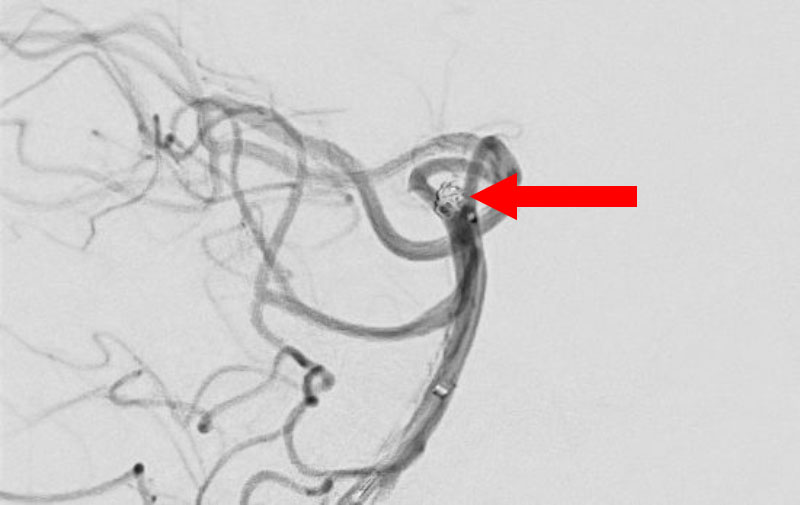

'25年11月

くも膜下出血

左中大脳動脈瘤破裂

40代

救急外来

No.1596 手術前

No.1596 手術中

No.1596 手術後